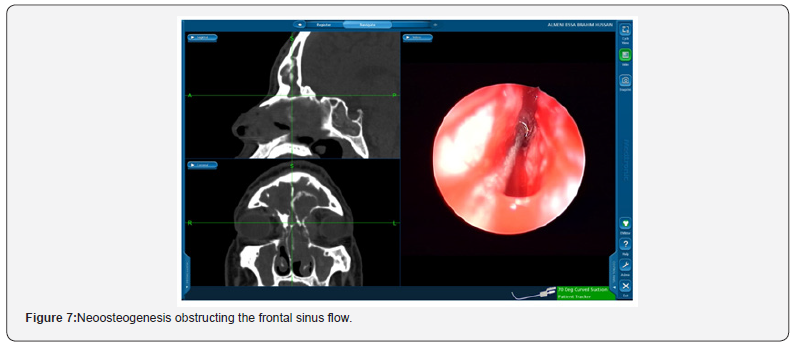

Suprabullar cells are also a recognizable cause of recurrence where is can be wronged for base of skull during primary surgery and left untouched [12]. That represents 11% of the findings in the revision cases in this study such as the illustrated case in Figure 5. In another recognizable cause 24% of the revised patients had lateralization of the middle turbinate Figure 6. This lateralization was found to be due to scarring between the turbinate and retained air cells or uncinate process 13%, 11% respectively. Other causes include neo-osteogenesis, which believed to be caused by failure to preserve normal mucosa [13]. Neo-osteogenesis as seen in Figure 7 presented 5% of our findings.